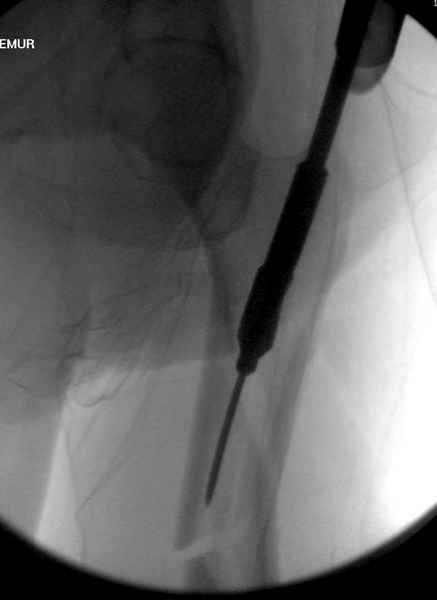

Для профилактики дальнейшего раскола в шейке предварительно во время проксимального рассверливания спереди и сзади провели временные спицы, которые в дальнейшем были заменены на шурупы (miss nail method)